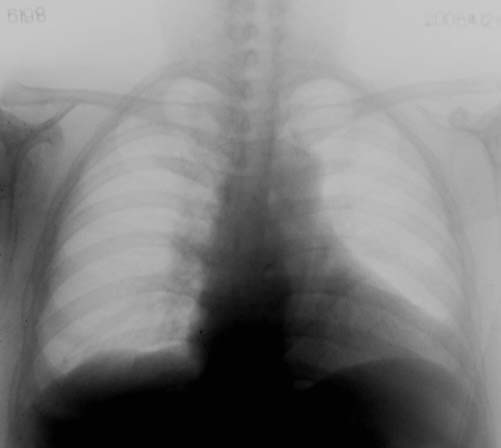

患者,女,63岁,胸闷,气促月余。请看左下肺是正常吗?还是心脏影还是胸膜反应?

只有正位患者横位心,再看也是猜.不过隐约可见肋膈角,应该没问题,是心包脂肪重叠的吧.最好透视转一下,就放心了.

病人是不是较肥,心脏呈横位,可在透视下观察看是否有异常。

赞同3楼的看法。肋膈角隐约可见,应当不是胸膜的病变。考虑为横位心及心包脂肪垫所致。

谢谢各位同行的指导!该病人是较胖的一个人,我用12x15胶片照的时候增感屏都是横起放的,要不是都照不起,当时我也考虑是心脏的重影,现在有各位的看法,也证实的我的这一点,因为停电,所以病人一照好以后便走了,所以没有照侧位,也没有机会透视看了。这一张片子我都是点着烟边抽边照边洗的。所以不怎么好看,呵呵!

考虑为横位心及心包脂肪垫所致

考虑:横位心+心包脂肪垫,透视旋转观察一下就准确。